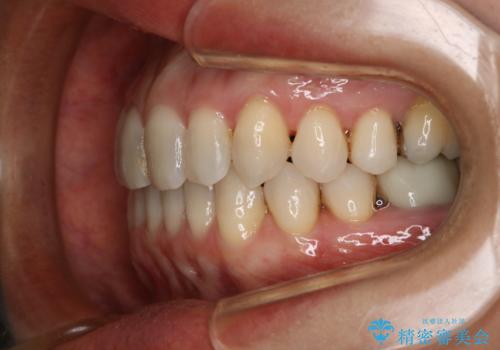

- 右上の小臼歯が二本とも90度捻じれてしまっており、奥歯の噛み合わせに問題が生じていました。

歯を抜いてワイヤー治療を行うという選択肢もありましたが、

奥歯の被せ物の形を適切にすることで非抜歯でも治療が可能であると判断し、

非抜歯、インビザラインでによるマウスピース矯正治療を行うことにいたしました。

今回は右上の奥歯に入っていた銀歯の形が悪く、そのせいで歯を並べるスペースが足りない状態でした。

右上の歯の被せ物を作りなおし、適切な歯の大きさに代えてあげることによってスペースを作りました。

また、それだけではスペースが足りない為右上の奥歯は遠心移動を行っています。